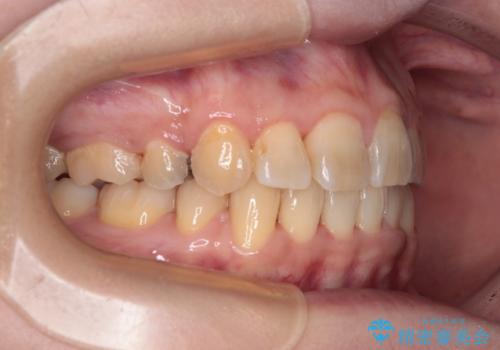

- 海外で抜歯矯正を開始し、治療途中で帰国したため、転院先を探しているとのことで来院された患者様です。

ワイヤーは抜けてしまい、後戻りが始まっている状態でしたが、既存の装置を継続利用して受け入れてくれる医院が見つからないとのことでした。